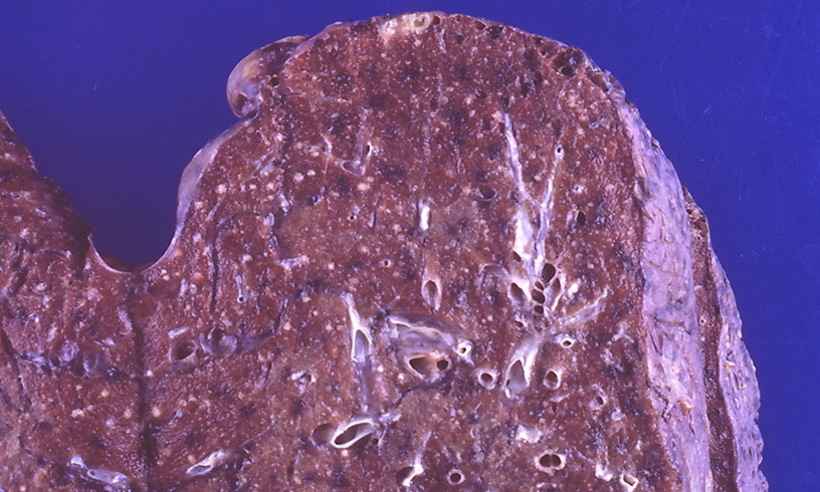

Микроскопический взгляд на мишитарный туберкулез легкого: фотодокументация